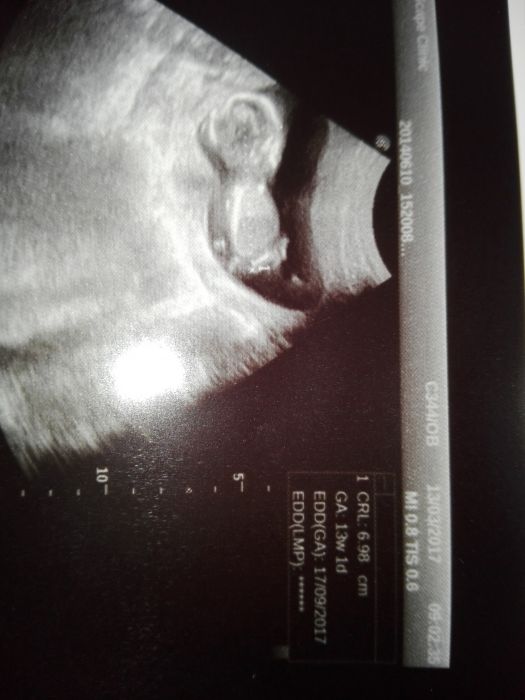

Tak i ja se pridavam s vybornymi vysledky ze screeningu

akorat teda prislo pro me trochu zklamani,ze to bude kluk,chtela jsem druhou holcicku

tak hlavne,ze je to zdravy